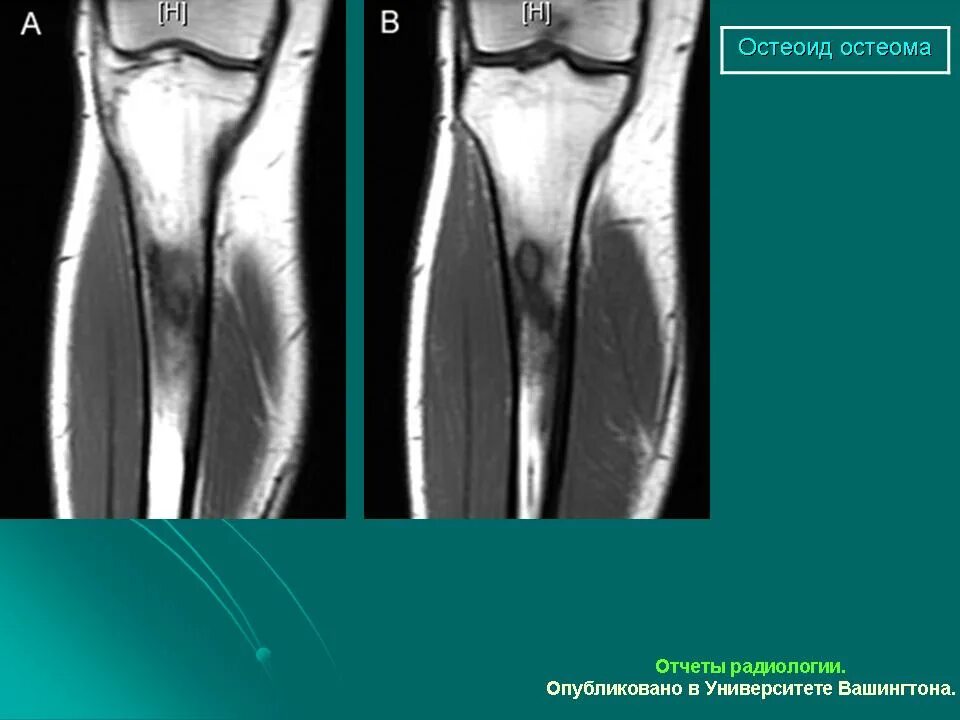

Остеома мрт